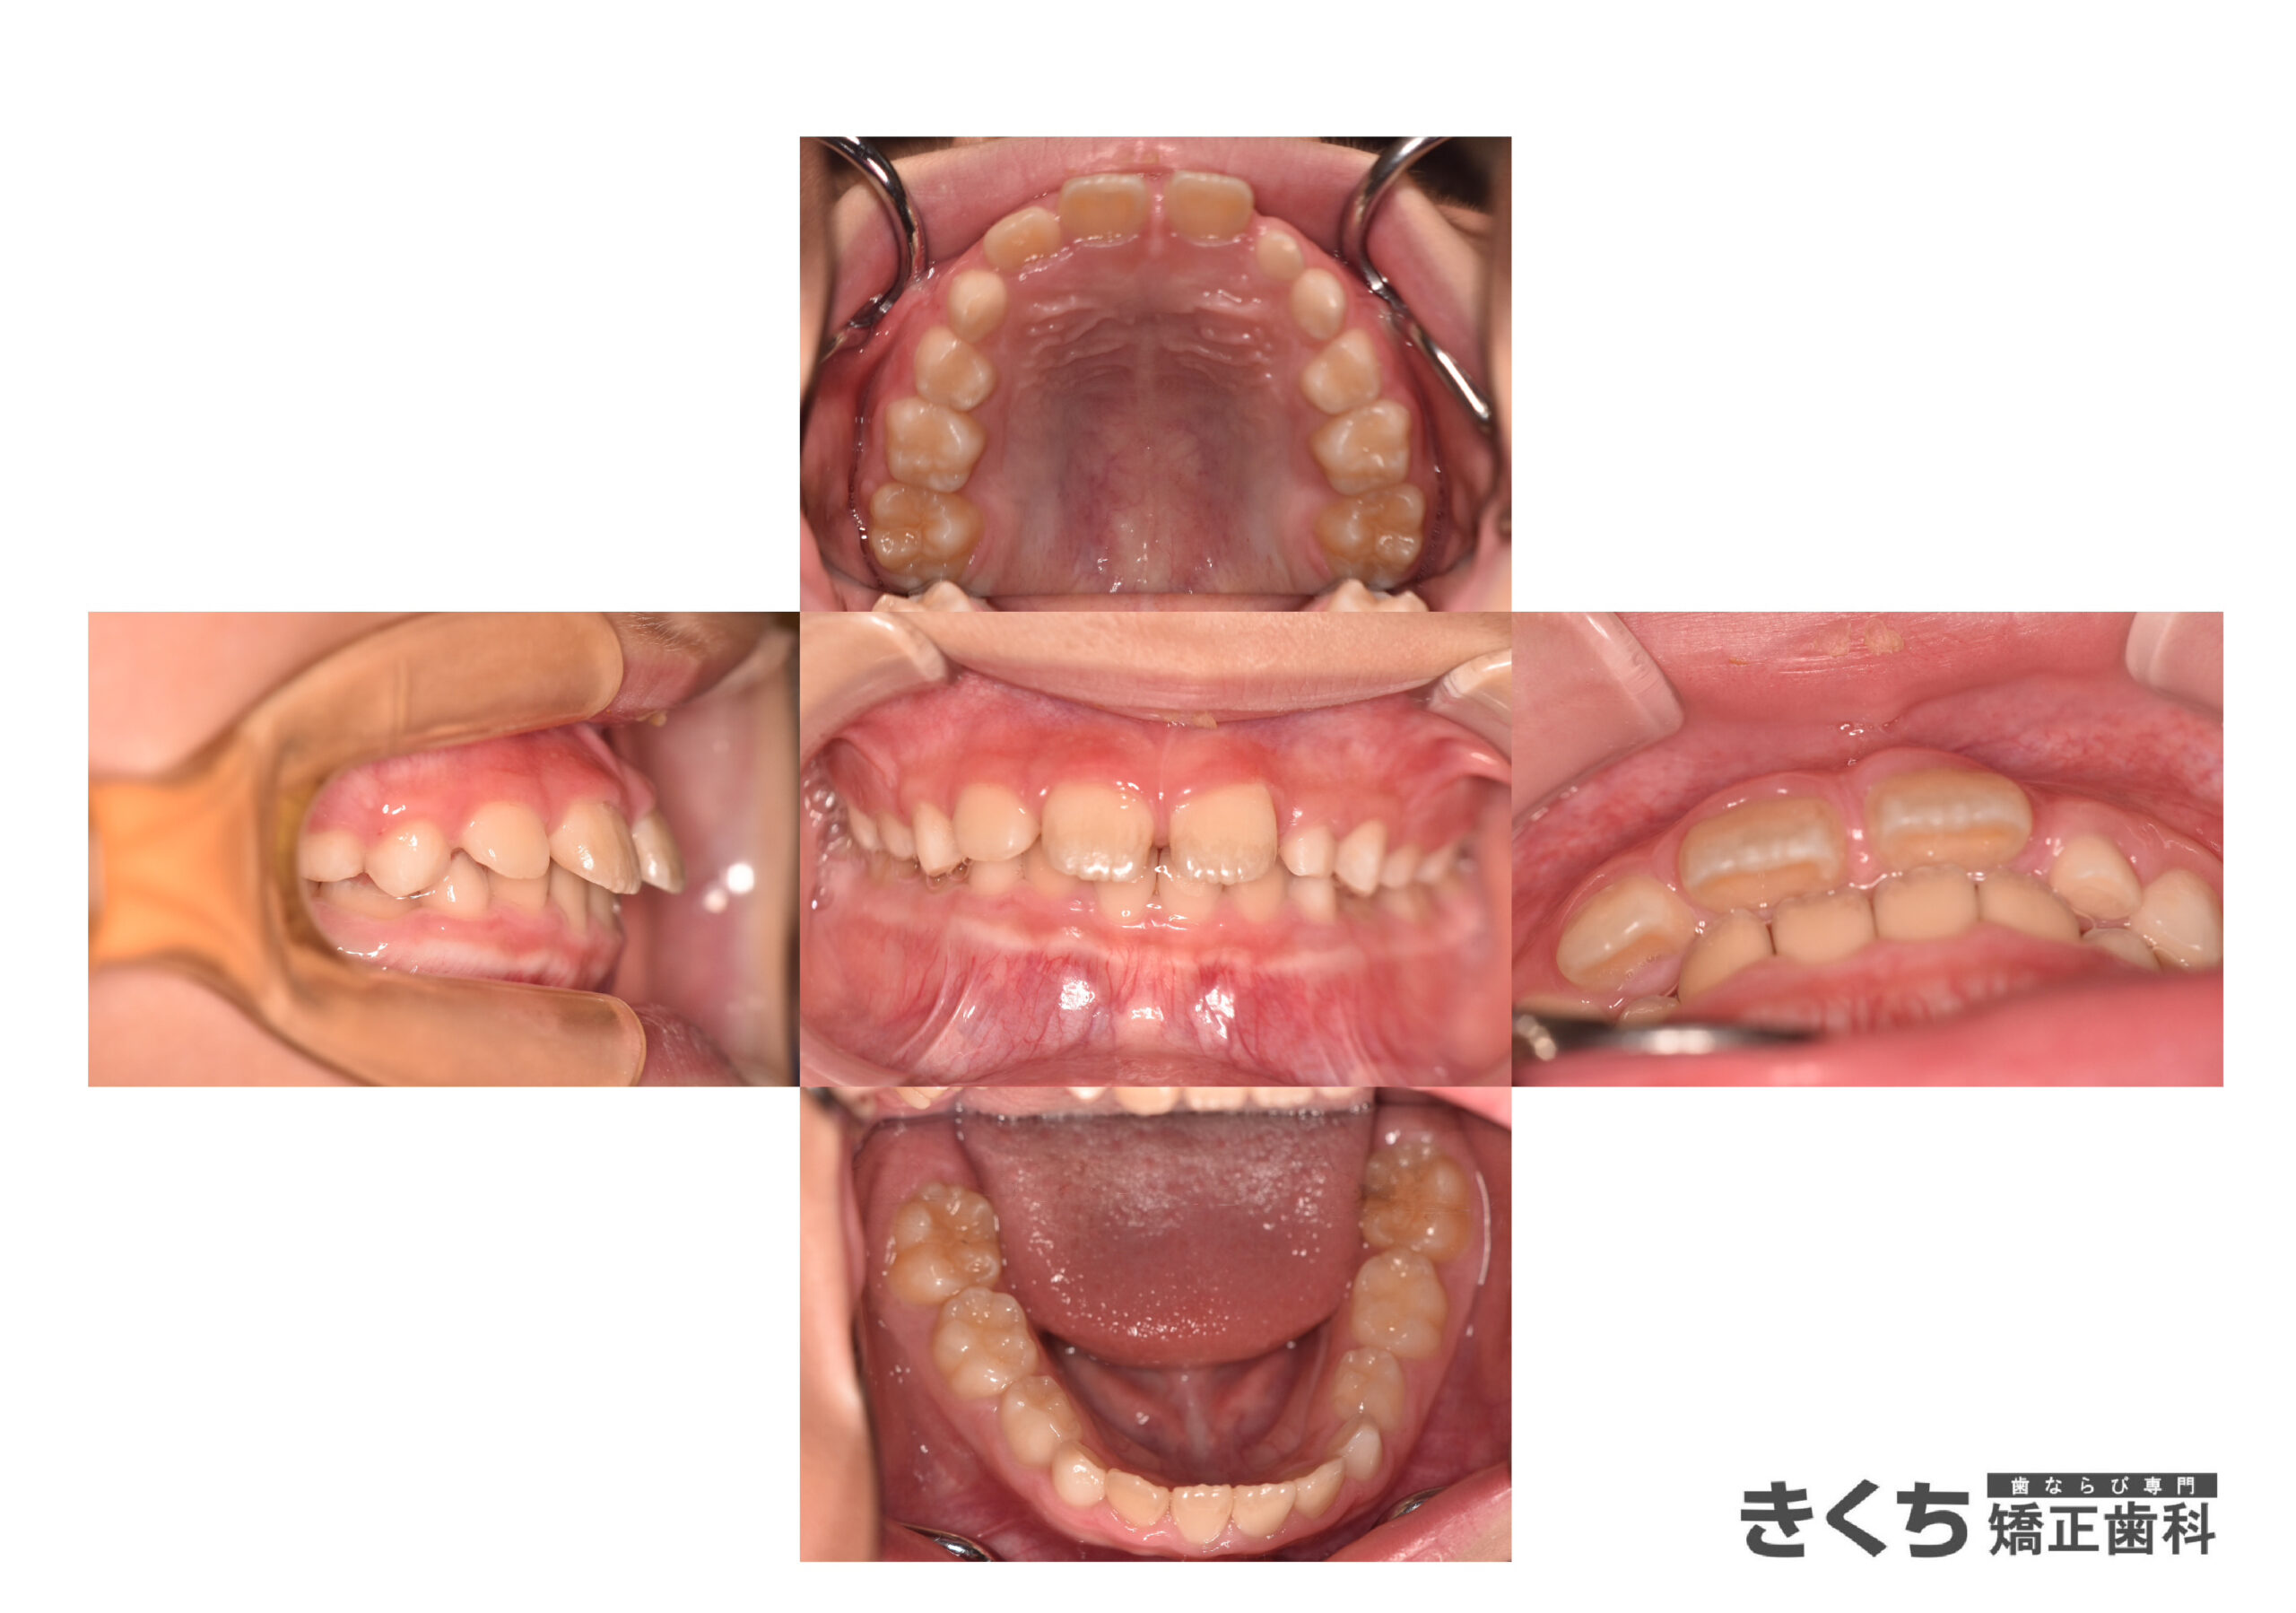

↓↓↓↓↓↓↓ 6ヶ月後

口腔筋機能 の改善だけで、気にしていたかみ合わせが自然に改善しました。